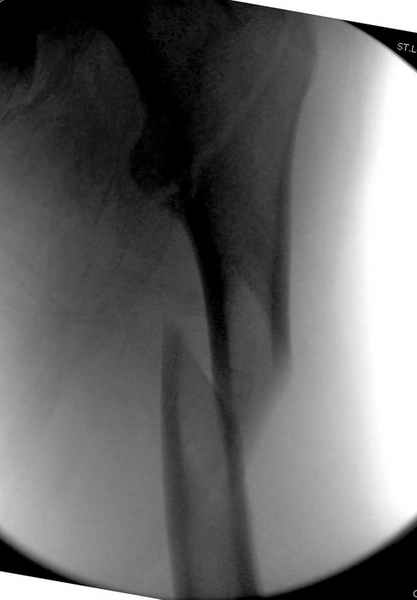

Как раз недавно у меня был примерный случай: больному 36 лет, поступил ночью, травма в результате мотоциклетной аварии, кроме чрезвертельного и спирального перелома левого бедра имеется переломы костей предплечья с этой же стороны. Скелетное вытяжение, а на следующий день больной про оперирован на ортопедическом столе с дистракцией. Чтобы не расколоть чрезвертельный перелом провели временную спицу ближе к переднему кортексу, из малого разреза костодержатель для репозиции, а фиксацию провели антиградным штифтом. Этапы операции на снимках.